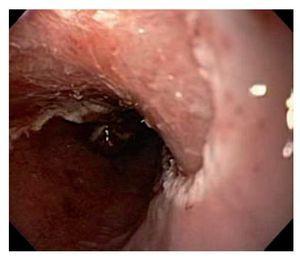

Hombre de 75 años de edad con pirosis de larga evolución y control médico irregular. Acude a realizarse endoscopia de tubo digestivo alto por hipo incoercible de reciente aparición. Durante el examen se observó mucosa sugestiva de esófago de Barret con lengüetas, la mayor de las cuales midió alrededor de 10 cm de longitud, con una circunferencia total de 7 cm (Praga C7M10), que involucraba los tercios medio y distal del esófago y sobre la cual se identificó una lesión polipoide de bordes irregulares de unos 10 mm de diámetro en el tercio medio del esófago que protruía hacia la luz (Figura 1). Se tomaron múltiples muestras para biopsia de dicha lesión que evidenciaron un adenocarcinoma bien diferenciado asociado al esófago de Barrett. Se realizó ultrasonido endoscópico (Olympus GFUCT140, Aloka alfa-5) que mostró engrosamiento focalizado de la pared esofágica de 3.4 mm x 4 mm que incluía mucosa y submucosa (Figura 2), además de observarse dos ganglios linfáticos subcarinales hipoecoicos redondos de 8 mm x 6 mm de los cuales se tomaron muestras para biopsia por aspiración con aguja fina que resultaron negativos para enfermedad maligna. En vista de la extensión de la lesión determinada por ultrasonido endoscópico, así como del riesgo de presentar metástasis ganglionares por el involucro de la lesión hasta la submucosa, pero debido al alto riesgo quirúrgico del paciente debido su edad y comorbilidades (hipertensión arterial sistémica, enfermedad isquémica reciente y enfermedad pulmonar obstructiva crónica avanzada), se decidió realizar una resección endoscópica de la lesión con el uso de capuchón transparente y ligas, previa elevación de la lesión con solución salina y epinefrina (Figura 3A, 3B), inyectando dicha solución en los bordes y la base de la lesión mediante aguja de escleroterapia. Después de la elevación, se realizó aspiración de la lesión en bloques con el capuchón transparente, una vez succionada una porción de la lesión se liberó una liga, después se introdujo el asa de polipectomía enlazando el tejido ligado y realizando el corte de esa porción de tejido. Se recuperaron con red tres piezas quirúrgicas de un tamaño cercano de 5 mm, cada una las cuales fue extendida con alfileres en una tabla, introducidas en formol y enviadas a estudio histopatológico, el cual reportó adenocarcinoma moderadamente diferenciado con ulceración focal, con infiltración de la lámina propia y la muscular de la mucosa, pero sin invasión de la submucosa ni invasión vascular; los bordes quirúrgicos fueron negativos para neoplasia. Dos meses después del procedimiento, el paciente se encuentra asintomático y en buenas condiciones generales (Figura 3C).

Figura 3B. Esófago postresección endoscópica de la mucosa.

Figura 3C. Esófago 2 meses después de la resección endoscópica de la mucosa.